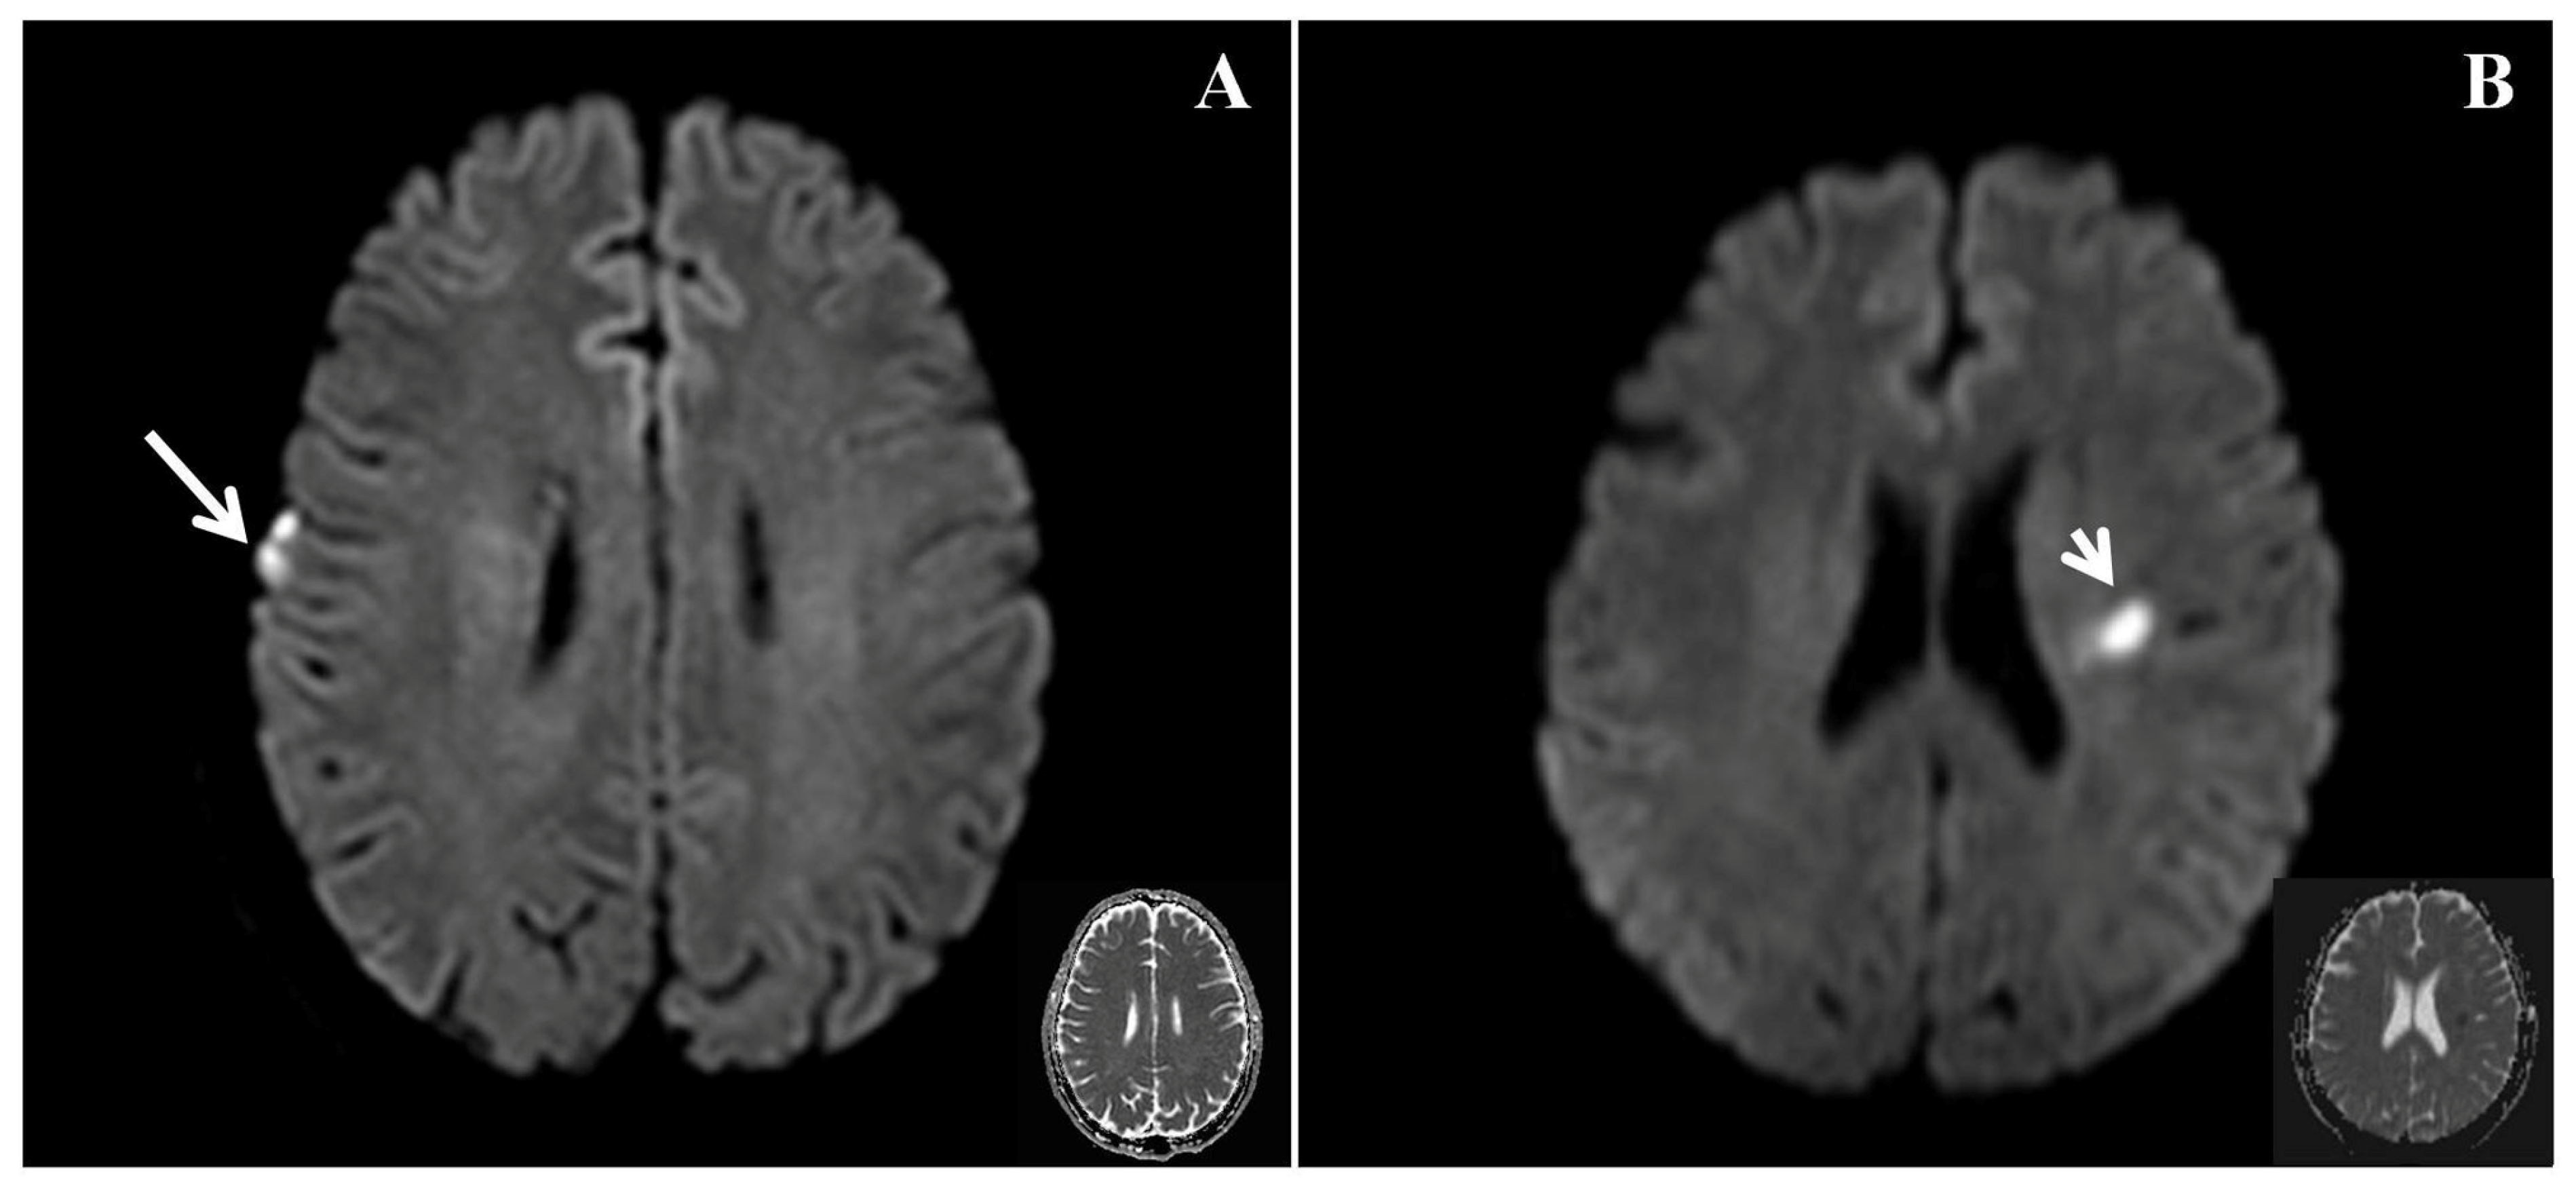

In the present study, the frequency of right cortical infarcts, significantly negatively correlated with EQ (Figure 2), with a standardized β value of −0.358. This finding suggests that the presence of right cortical infarcts is associated with a lower EQ, indicating poorer empathy. Ischemic brain injury can lead to the impairment of empathy. Leigh et al. studied 27 patients with acute right hemisphere ischemic stroke and 24 neurologically intact inpatients using a test of affective empathy [4], and found that an acute impairment of affective empathy is associated with infarcts in the temporal pole and anterior insula. Another study showed that stroke involving the right posterior superior temporal gyrus in the right hemisphere ventral stream was critical for the identification of emotion in speech [10]. This finding suggests that patients who have experienced stroke and infarction in this area should be assessed for the impairment of emotion. Although these studies were inconclusive, they suggest that a network may play a major role in the processing of empathy. The present findings are consistent with the notion that the right cortical region may play an important role in the recognition of emotion.

Figure 2.

Diffusio-weighted imaging (DWI) and the corresponding apparent diffusion coefficient (ADC) in patients with differing empathy statuses. (A) A patient with an EQ of 16 (poorer empathy) had an acute infarct involving the right frontal lobe marked by a long arrow (right cortical infarct) during the acute phase. (B) A patient with an EQ of 73 (better empathy) had an acute infarct in the left corona radiata marked by a short arrow (left subcortical infarct) during the acute phase.